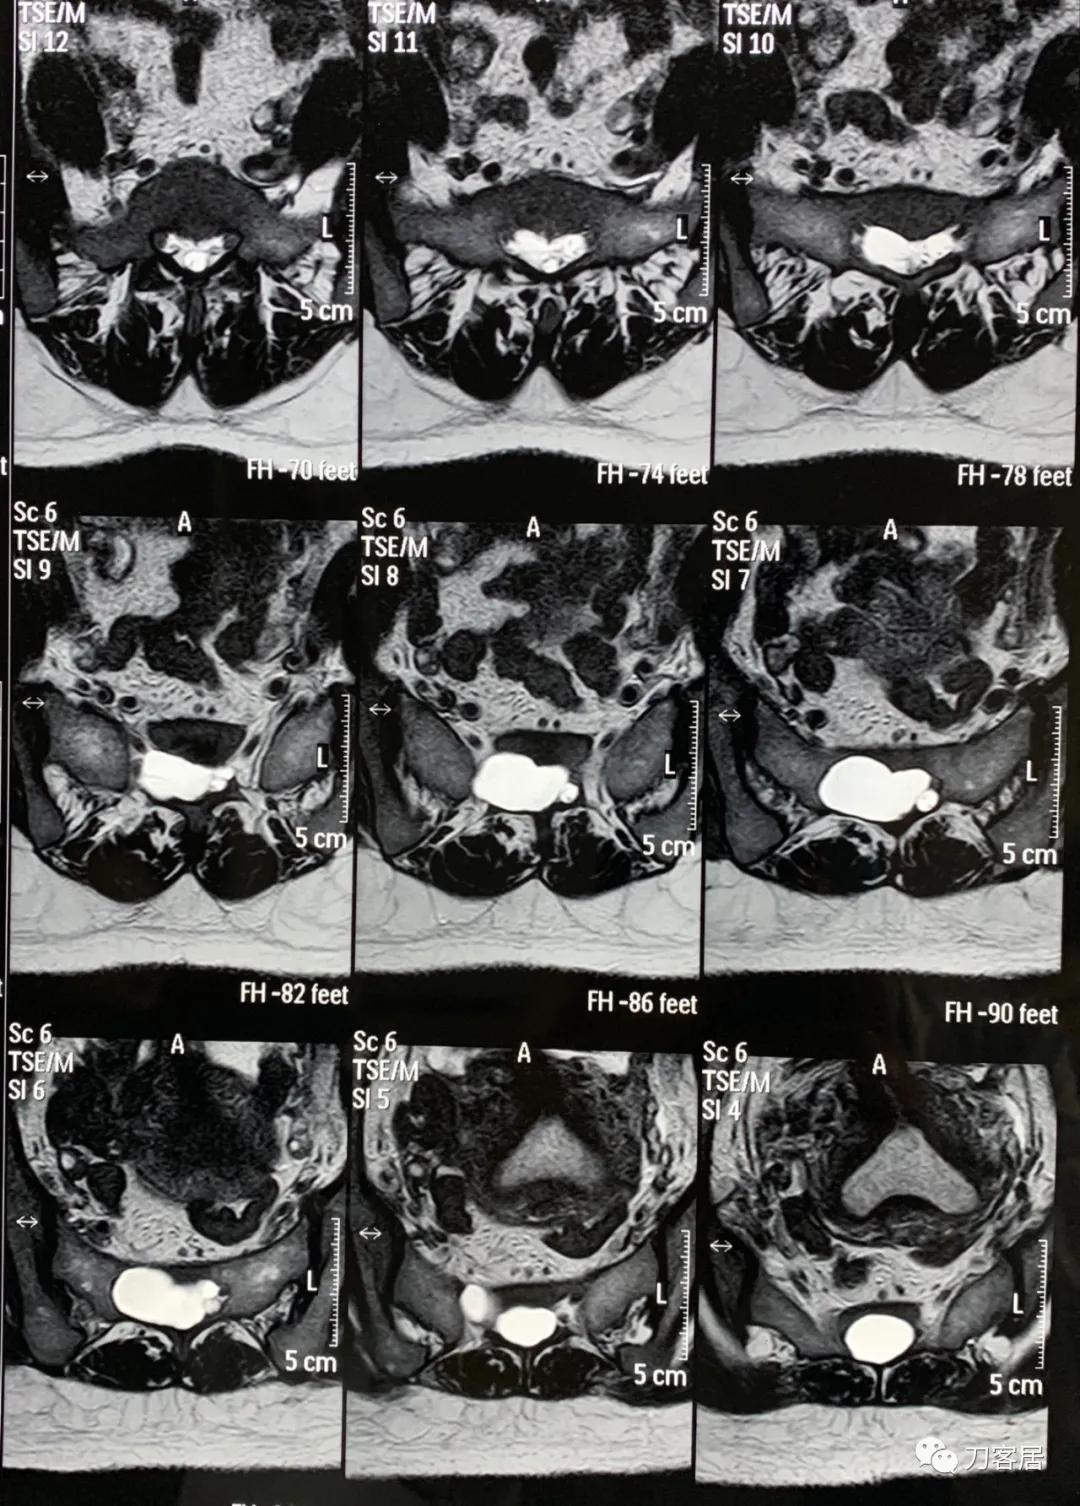

20160217患者骶管囊肿术前的腰骶椎磁共振

20160912患者骶管囊肿术后的腰骶椎磁共振